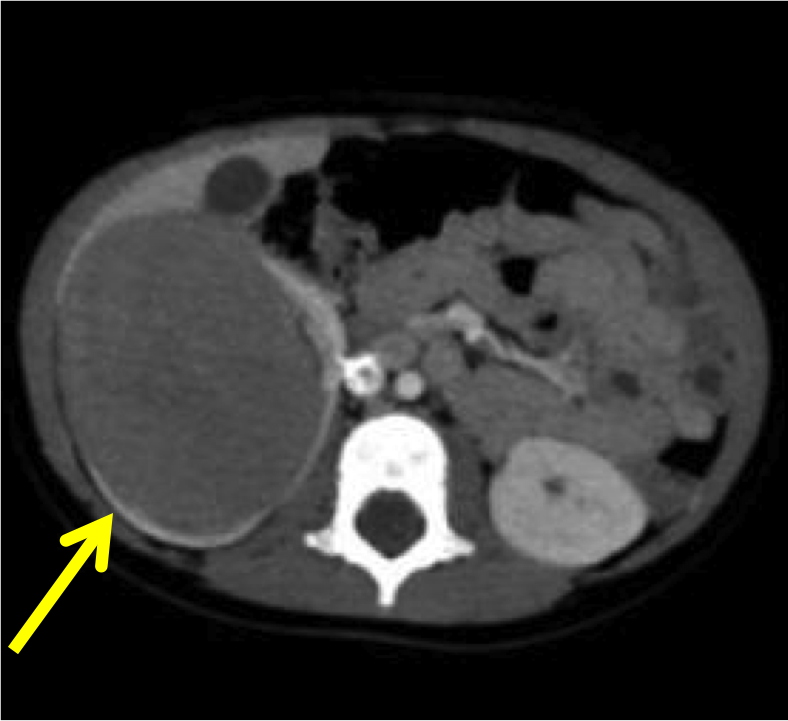

Al bilancio di salute del 1� anno di vita di Ryan, un bel bambino asintomatico e in ottime condizioni generali, il pediatra riscontra una massa addominale in ipocondrio destro, per cui lo invia in PS per ulteriori accertamenti. All'arrivo in PS il bambino � spaventato dalla presenza di tanti visi nuovi, non si lascia visitare, piange e scalcia, mentre dal curante si lasciava valutare tranquillo. Gli esami ematici sono nella norma, salvo per lieve leucocitosi linfocitaria e minimo aumento dell'LDH. L'ecografia addominale conferma il sospetto del curante, con evidenza in ipocondrio destro di una formazione solida rotondeggiante di 7 cm isoecogena al parenchima renale, dislocante il rene destro. Nel sospetto di neoplasia, viene eseguita TAC total body che conferma la presenza della massa senza altri reperti significativi (Figure).

Considerato l'imaging suggestivo di nefroblastoma localizzato e l'assenza di fattori di rischio chirurgici, Ryan viene subito sottoposto a intervento di nefroureterectomia destra con risparmio del surrene omolaterale e asportazione radicale della massa, con conferma istologica di tumore di Wilms, stadio I. Per il riscontro di microinfiltrazione capsulare il piccolo viene avviato a chemioterapia neoadiuvante di 6 settimane secondo il protocollo AIEOP (vincristina e actinomicina D), ben tollerata, con remissione completa di malattia.